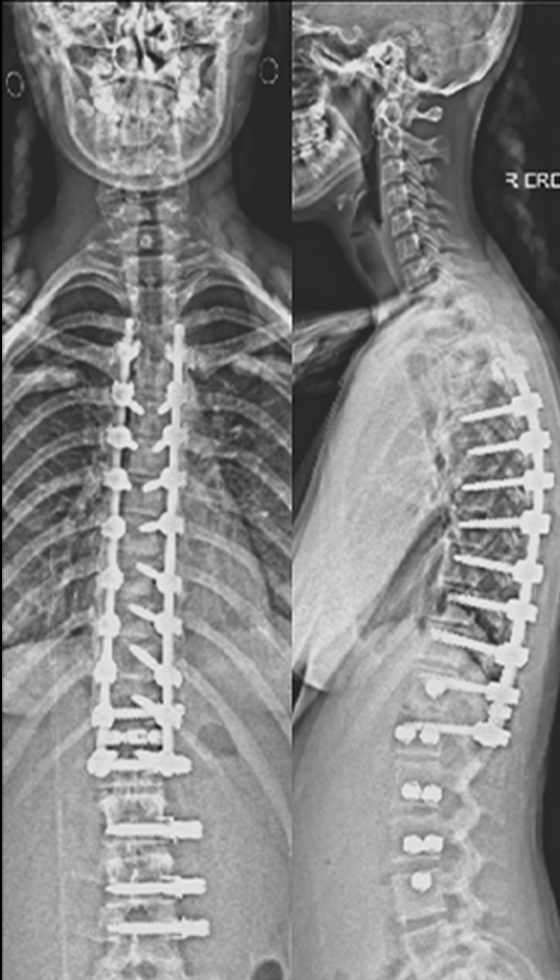

The procedure involves repositioning the spine and securing it with Screws and Rods. Bone graft is then placed so the treated vertebrae gradually heal together into one solid segment. This creates long-term stability, preventing further curve progression and improving overall alignment.

Gallery : Before - After

After

Before